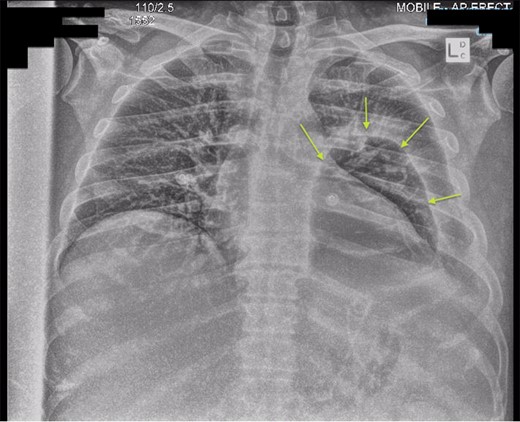

Chest X-ray in ICU following drainage showed what was thought to be Pneumomediastinum (Figs 1 and 2), and given this concern he was referred to the Cardiothoracic service. Subsequent CT suggested a large loculated hydro-pneumothorax, which in retrospect represented the drained Pseudocyst communicating through the diaphragm (Figs 3 and 4).

Chest X-ray post-transgastric drainage. Area of residual space highlighted with arrows.